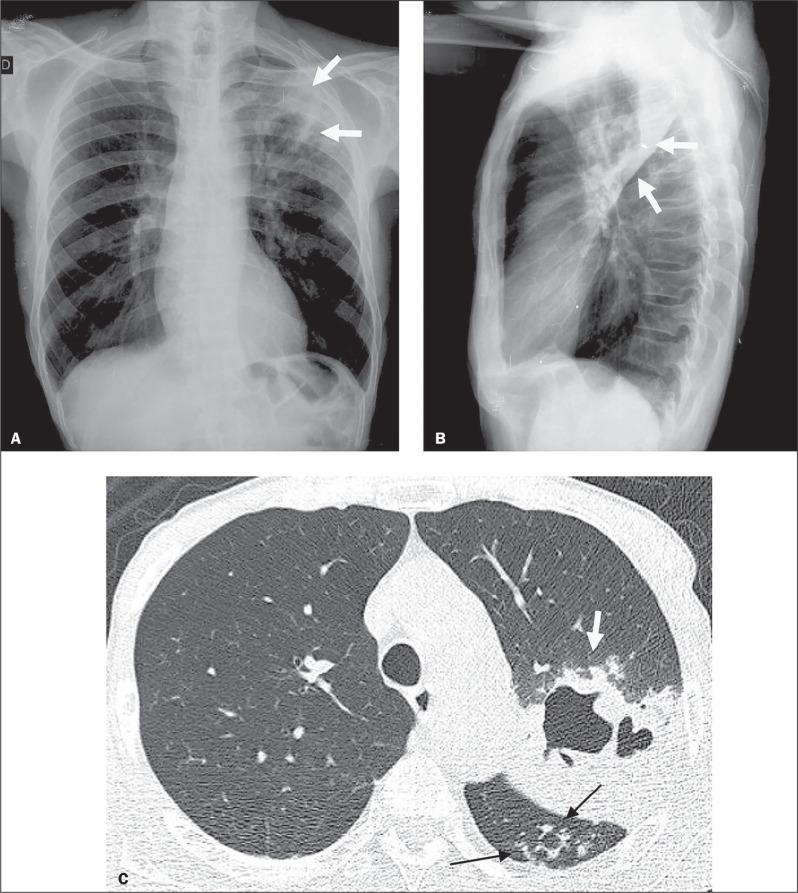

肾移植受者活动性肺结核的放射学表现:4例回顾性研究及文献复习

Radiological presentation of active pulmonary tuberculosis in kidney transplant recipients: a retrospective study of four cases and a review of the literature.

Although kidney transplantation is the best therapeutic option for patients with chronic kidney disease, the immunosuppression required greatly increases susceptibility to infections that are responsible for high post-transplant mortality. Pulmonary tuberculosis (TB) represents a major cause of such infections, and its early diagnosis is therefore quite important. In view of that, we researched the manifestations of active pulmonary TB in kidney transplant recipients, through chest X-ray and computed tomography (CT), as well as determining the number of cases of active pulmonary TB occurring over a 3.5-year period at our institution. We identified four cases of active pulmonary TB in kidney transplant recipients. The CT scans provided information complementary to the chest X-ray findings in all four of those cases. We compared our CT findings with those reported in the literature. We analyzed our experience in conjunction with an extensive review of the literature that was nevertheless limited because few studies have been carried out in lowand middle-income countries, where the incidence of TB is higher.

尽管肾移植是慢性肾病患者的最佳治疗选择,但所需的免疫抑制会大大增加感染易感性,而感染是移植后高死亡率的原因。肺结核(TB)是此类感染的主要原因,因此其早期诊断非常重要。有鉴于此,我们通过胸部X光和计算机断层扫描(CT)研究了肾移植受者活动性肺结核的表现,并确定了我院3.5年期间发生的活动性肺结核病例数。我们在肾移植受者中发现了4例活动性肺结核病例。在所有这4例病例中,CT扫描提供了与胸部X光检查结果互补的信息。我们将我们的CT检查结果与文献报道的结果进行了比较。我们结合对文献的广泛回顾分析了我们的经验,不过文献回顾有限,因为在结核病发病率较高的低收入和中等收入国家开展的研究很少。